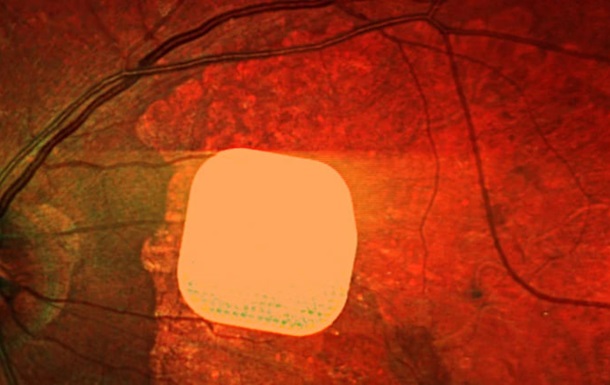

Мікрочип розміром лише 2×2 міліметри і завтовшки з половину людської волосини хірургічно встановлюють під сітківку ока. Під час операції, що триває менше двох годин, пацієнту також під’єднують систему окулярів доповненої реальності з камерою і мінікомп’ютером. Камера зчитує навколишнє зображення, перетворює його на інфрачервоний сигнал і передає на мікрочип, який активує клітини сітківки. Потім через зоровий нерв сигнал надходить до мозку, утворюючи візуальне сприйняття.

У дослідженні взяли участь 38 пацієнтів із “сухою” формою вікової макулодистрофії. До операції вони повністю втратили центральний зір і могли бачити лише периферійно. Після імплантації та періоду адаптації 84% учасників знову змогли розрізняти літери, цифри та слова.